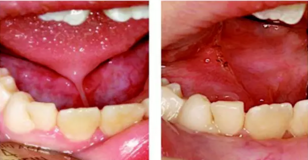

激光軟組織治療的范圍很廣,本文僅以圖片介紹最常見的病變牙齦切除 、系帶切除術 、修復治療中代替壓排線放置的牙齦處理、種植體暴露和牙齦成形術。

1. 病變牙齦切除

2. 舌系帶切除